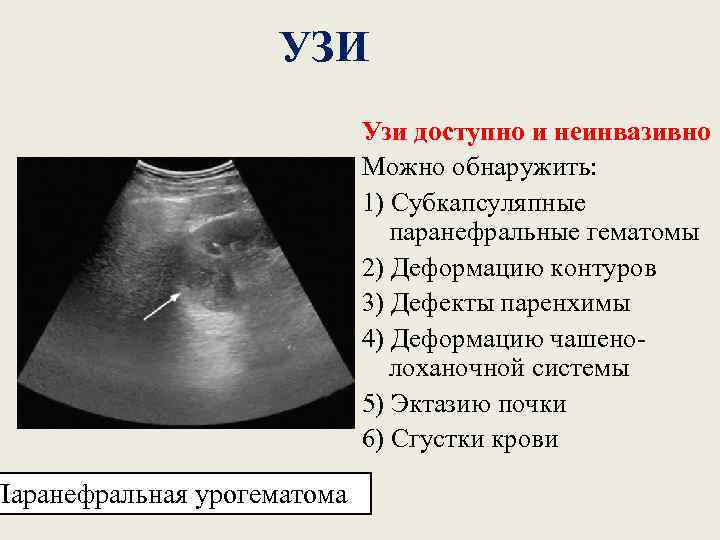

УЗИ Паранефральная урогематома Узи доступно и неинвазивно Можно обнаружить: 1) Cубкапсуляпные паранефральные гематомы 2) Деформацию контуров 3) Дефекты паренхимы 4) Деформацию чашенолоханочной системы 5) Эктазию почки 6) Сгустки крови

Подкапсульная гематома почки Гематома в паранефральной клетчатке

Разрыв почечной паренхимы с повреждением капсулы, коллекторной системы и обширной паранефральной гематомой.